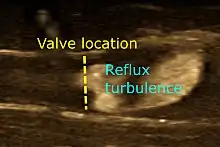

Doppler ultrasonography is used to study blood flow and muscle motion. The different detected speeds are represented in color for ease of interpretation, for example leaky heart valves: the leak shows up as a flash of unique color. Colors may alternatively be used to represent the amplitudes of the received echoes.

Doppler ultrasonography employs the Doppler effect to assess whether structures (usually blood)[55][58] are moving towards or away from the probe, and their relative velocity. By calculating the frequency shift of a particular sample volume, flow in an artery or a jet of blood flow over a heart valve, its speed and direction can be determined and visualized, as an example. Color Doppler is the measurement of velocity by color scale. Color Doppler images are generally combined with gray scale (B-mode) images to display duplex ultrasonography images.[59] Uses include:

- Doppler echocardiography is the use of Doppler ultrasonography to examine the heart.[60] An echocardiogram can, within certain limits, produce accurate assessment of the direction of blood flow and the velocity of blood and cardiac tissue at any arbitrary point using the Doppler effect. Velocity measurements allow assessment of cardiac valve areas and function, abnormal communications between the left and right side of the heart, leaking of blood through the valves (valvular regurgitation), and calculation of the cardiac output and E/A ratio[61] (a measure of diastolic dysfunction). Contrast-enhanced ultrasound using gas-filled microbubble contrast media can be used to improve velocity or other flow-related measurements of interest.

Echocardiography is an essential tool in cardiology, assisting in evaluation of heart valve function, such as stenosis or insufficiency, strength of cardiac muscle contraction, and hypertrophy or dilatation of the main chambers. (ventricle and atrium)